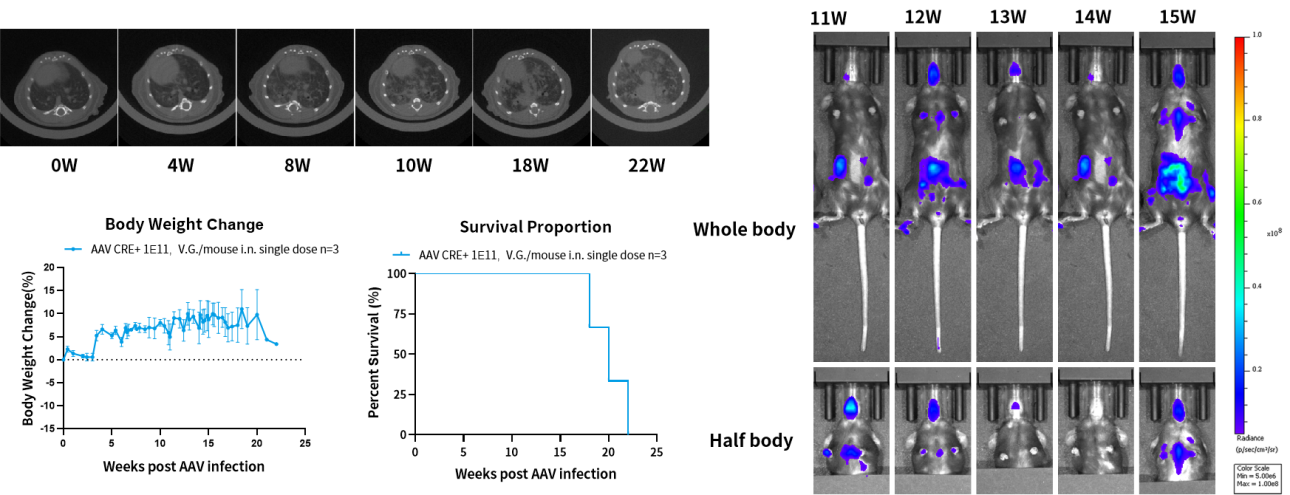

Trp53-Flox/Kras-LSL-G12D小鼠是一种原发肺癌小鼠模型,包含了Kras基因G12D突变与Trp53蛋白缺失。编码肿瘤抑制因子Trp53在绝大多数小细胞肺癌(SCLC)肿瘤中失活。野生型Kras激活/失活效应是受控的,而突变型Kras蛋白功能异常,持续处于激活状态,导致肿瘤细胞的持续增殖。相似的,通过使用AAV-CRE对小鼠进行诱导,可使该模型小鼠产生肿瘤。

图4. Trp53-Flox/Kras-LSL-G12D原发肺癌小鼠模型可通过AAV-CRE诱导引发肺癌。